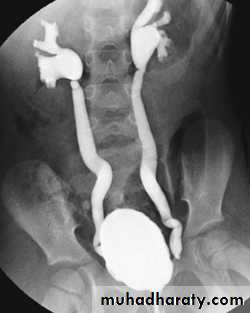

Voiding cystourethrogram (micturating cystogram)Retrograde urethrogram

Strictures of any portion of the pelvicaliceal system or ureter may occur, producing dilatation of one or more calices. The multiplicity of strictures is an important diagnostic feature.

If the bladder is involved, the wall is irregular because of inflammatory edema; advanced disease causes fibrosis resulting in a thick-walled small volume bladder.

Multiple strictures may be seen in the urethra.

Vesicoureteric reflux may be demonstrated at micturating (voiding) cystography.